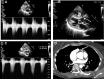

Tetralogy of Fallot (TOF) is a heterogeneous congenital heart disease that is occasionally diagnosed during adulthood. However, although they are often asymptomatic, adult patients with uncorrected TOF often have a poor prognosis. Poor outcomes indicate the importance of the identification and management of these patients, especially in the context of intercurrent disease or noncardiac surgery. We describe a case of clinically silent TOF in a 51-year-old woman. TOF was unmasked during a major noncardiac surgery for a polytrauma and successfully treated with the cooperation of a multidisciplinary team. (Level of Difficulty: Advanced.).